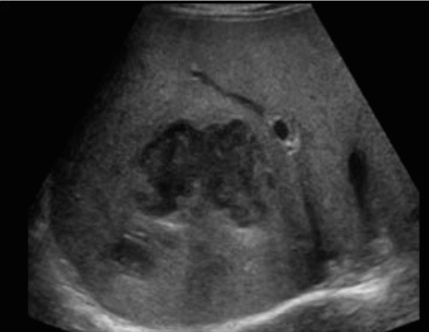

- 원형으로 경계가 분명한 단순낭종이다.

- 큰 낭종 안에 작은 낭종이 존재(daughter cyst)

- 낭종벽내 석회화가 관찰된다 (cyst wall calcification)

- 백합모양(water-lily sign)

daughter cyst and water-lily sign ②아메바성 간농양 (amoebic abscess)